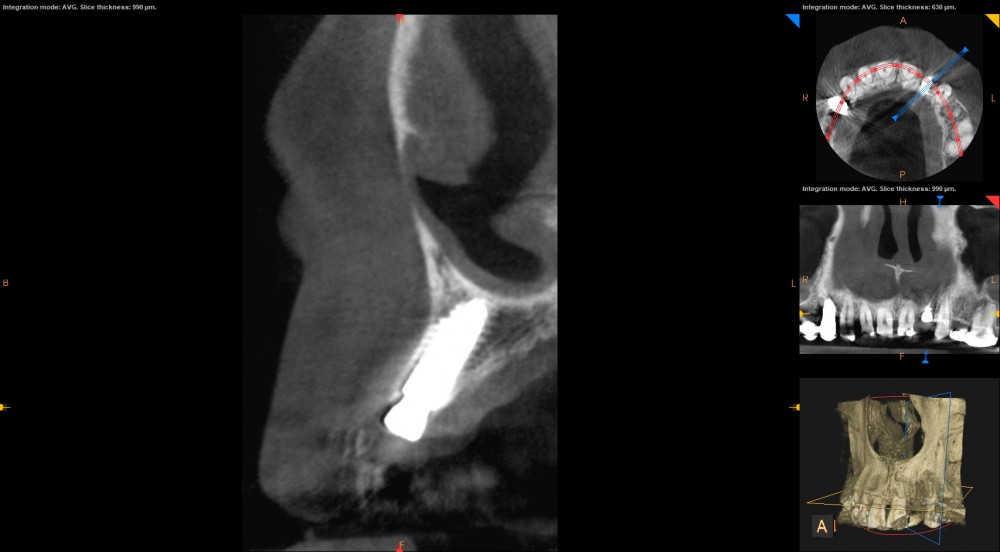

Pozycjonowanie implantów zębowych do niedawna uzależnione było wyłącznie od wiedzy, doświadczenia i chirurgicznej intuicji implantologa. Technologia CAD-CAM otworzyła wrota świadomej i bezpiecznej chirurgii szczepowej. Szablon chirurgiczny powstaje w drodze nałożenia obrazu otrzymanego dzięki skanowaniu z obrazem z CBCT (tomografia). Lekarz otrzymuje precyzyjny i rzeczywisty obraz tkanek w obrębie jamy ustnej pacjenta. Na tej podstawie ocenia ilość, gęstość i wymiary wyrostka zębodołowego oraz biotyp tkanki miękkiej, aby dostosować idealny kształt i rozmiar implantów.